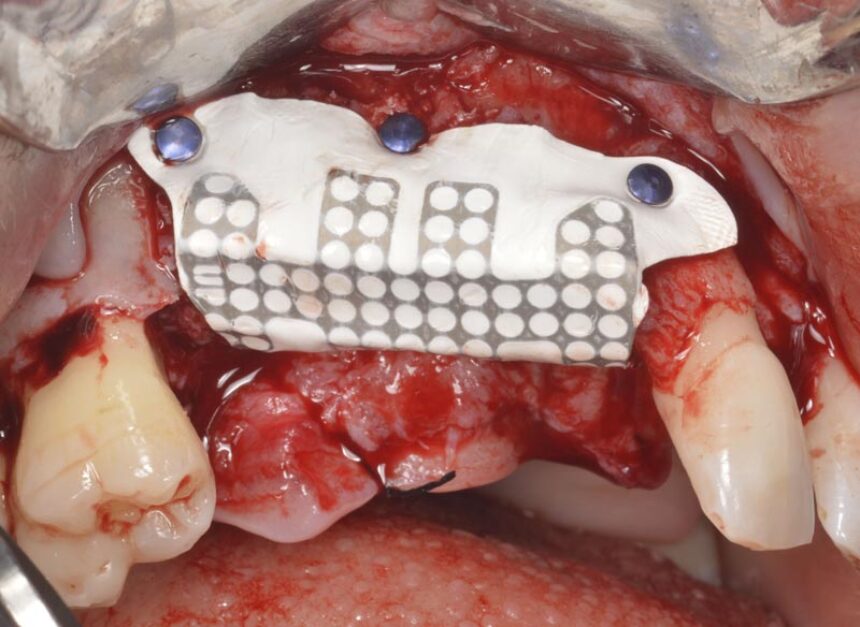

Πιο συγκεκριμένα, ο Prof. Massimo Simion, είναι ένας από τους πρωτεργάτες της διαδικασίας της Κατευθυνόμενης Οστικής Αναγέννησης στο χώρο της εμφυτευματολογίας. Μέσα από την τριαντακοετή εμπειρία του θα μας μεταφέρει τις εμπειρίες του στο χώρο αυτό καθώς και τα μυστικά επιτυχίας σε περιστατικά εκτενούς έλλειψης της φατνιακής ακρολοφίας τόσο στην άνω, όσο και στην κάτω γνάθο, αλλά και θα παρουσιάσει την αντιμετώπιση διαφόρων επιπλοκών που μπορεί να προκύψουν στην αντιμετώπιση αυτών των περιστατικών που αποτελούν πρόκληση για τους κλινικούς.

Κατηγοριοποίηση ατροφικού οστού των γνάθων – Σχεδιασμός θεραπείας και χειρουργικές ενδείξεις. Η πλήρως νωδή άνω γνάθος: διάφορες ατροφίες και αντίστοιχες χειρουργικές τεχνικές – Βίντεο με οστικά μοσχεύματα και Καθοδηγούμενη Οστική Ανάπλαση (GBR).

Η πλήρως νωδή κάτω γνάθος: διάφορες ατροφίες και αντίστοιχες χειρουργικές τεχνικές – Κοντά εμφυτεύματα - Οστικά μοσχεύματα – GBR

Οριζόντια και Κάθετη Αύξηση της Ακρολοφίας: χειρουργικό υπόβαθρο - χειρουργικές τεχνικές – απορροφήσιμες και μη-απορροφήσιμες μεμβράνες – λήψη οστικού μοσχεύματος από ενδο-στοματικά σημεία – βίντεο